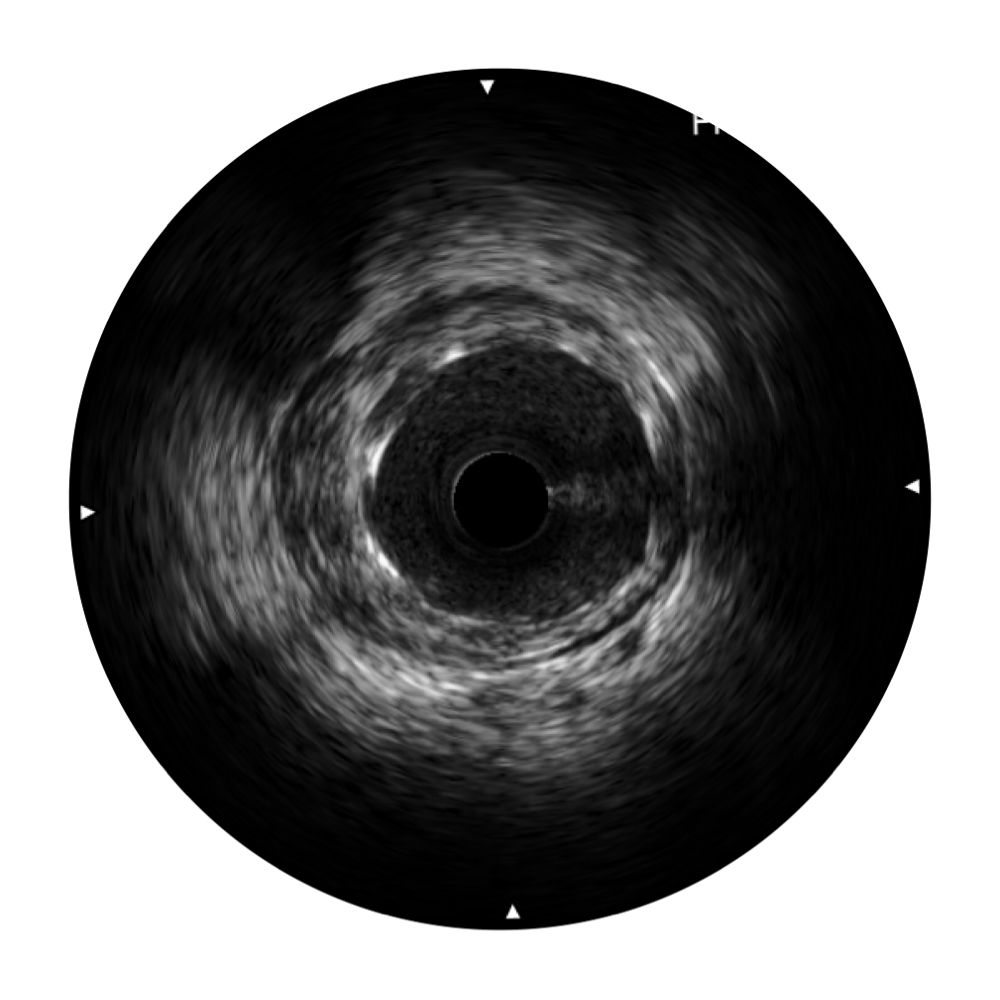

16877太阳集团宽频IVUS图像

传统IVUS图像

对比传统IVUS导管成像,16877太阳集团宽频IVUS图像的近场支架梁显影更细腻,远场中膜外血管仍清晰可辨,兼顾远中近,兼顾分辨力与穿透深度